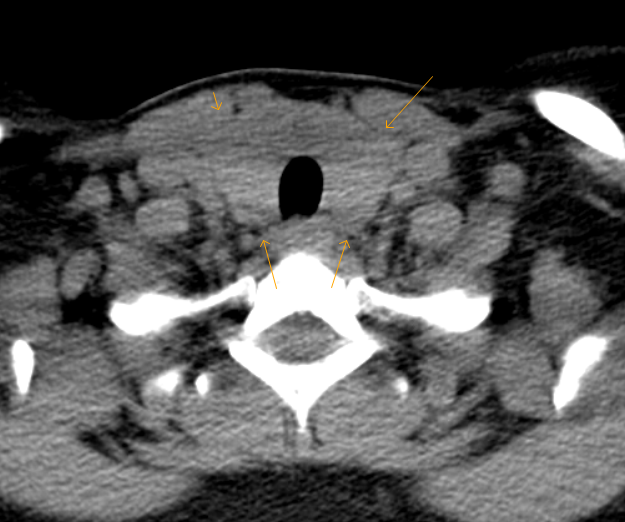

CT scan of neck showing enlarged thyroid with decreased density in some What Does Low Density Mean On A Ct Scan By small we usually mean less. Hyperdense refers to an area on the ct scan that appears brighter or denser than the surrounding. a common incidental finding on ct is a small low density lesion of the pancreas. low density on ct is the manifestation of any of the acute or. low density lesions include edema and. What Does Low Density Mean On A Ct Scan.

CT image of a low density formation in the retropharyngeal space at the What Does Low Density Mean On A Ct Scan a common incidental finding on ct is a small low density lesion of the pancreas. low density on ct is the manifestation of any of the acute or. By small we usually mean less. Hyperdense refers to an area on the ct scan that appears brighter or denser than the surrounding. for that reason, we also use. What Does Low Density Mean On A Ct Scan.